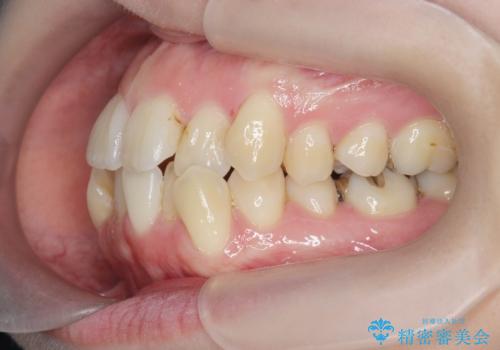

前歯のがたつき すれ違い咬合のマウスピース矯正治療

- 前歯のがたつきや歯の角度、矯正治療を希望され来院されました。

仕事の都合で、ワイヤー矯正を行うことが難しくマウスピース矯正であれば可能、という希望でした。

下顎が前にある咬合関係を可及的に咬合移動で改善し、IPR、下顎3前歯の仕上げで行うマウスピース矯正を計画します。